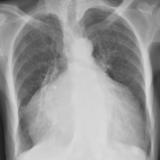

Cardiomegaly, esp RA PA

Date: 01/26/2009

Views: 2921